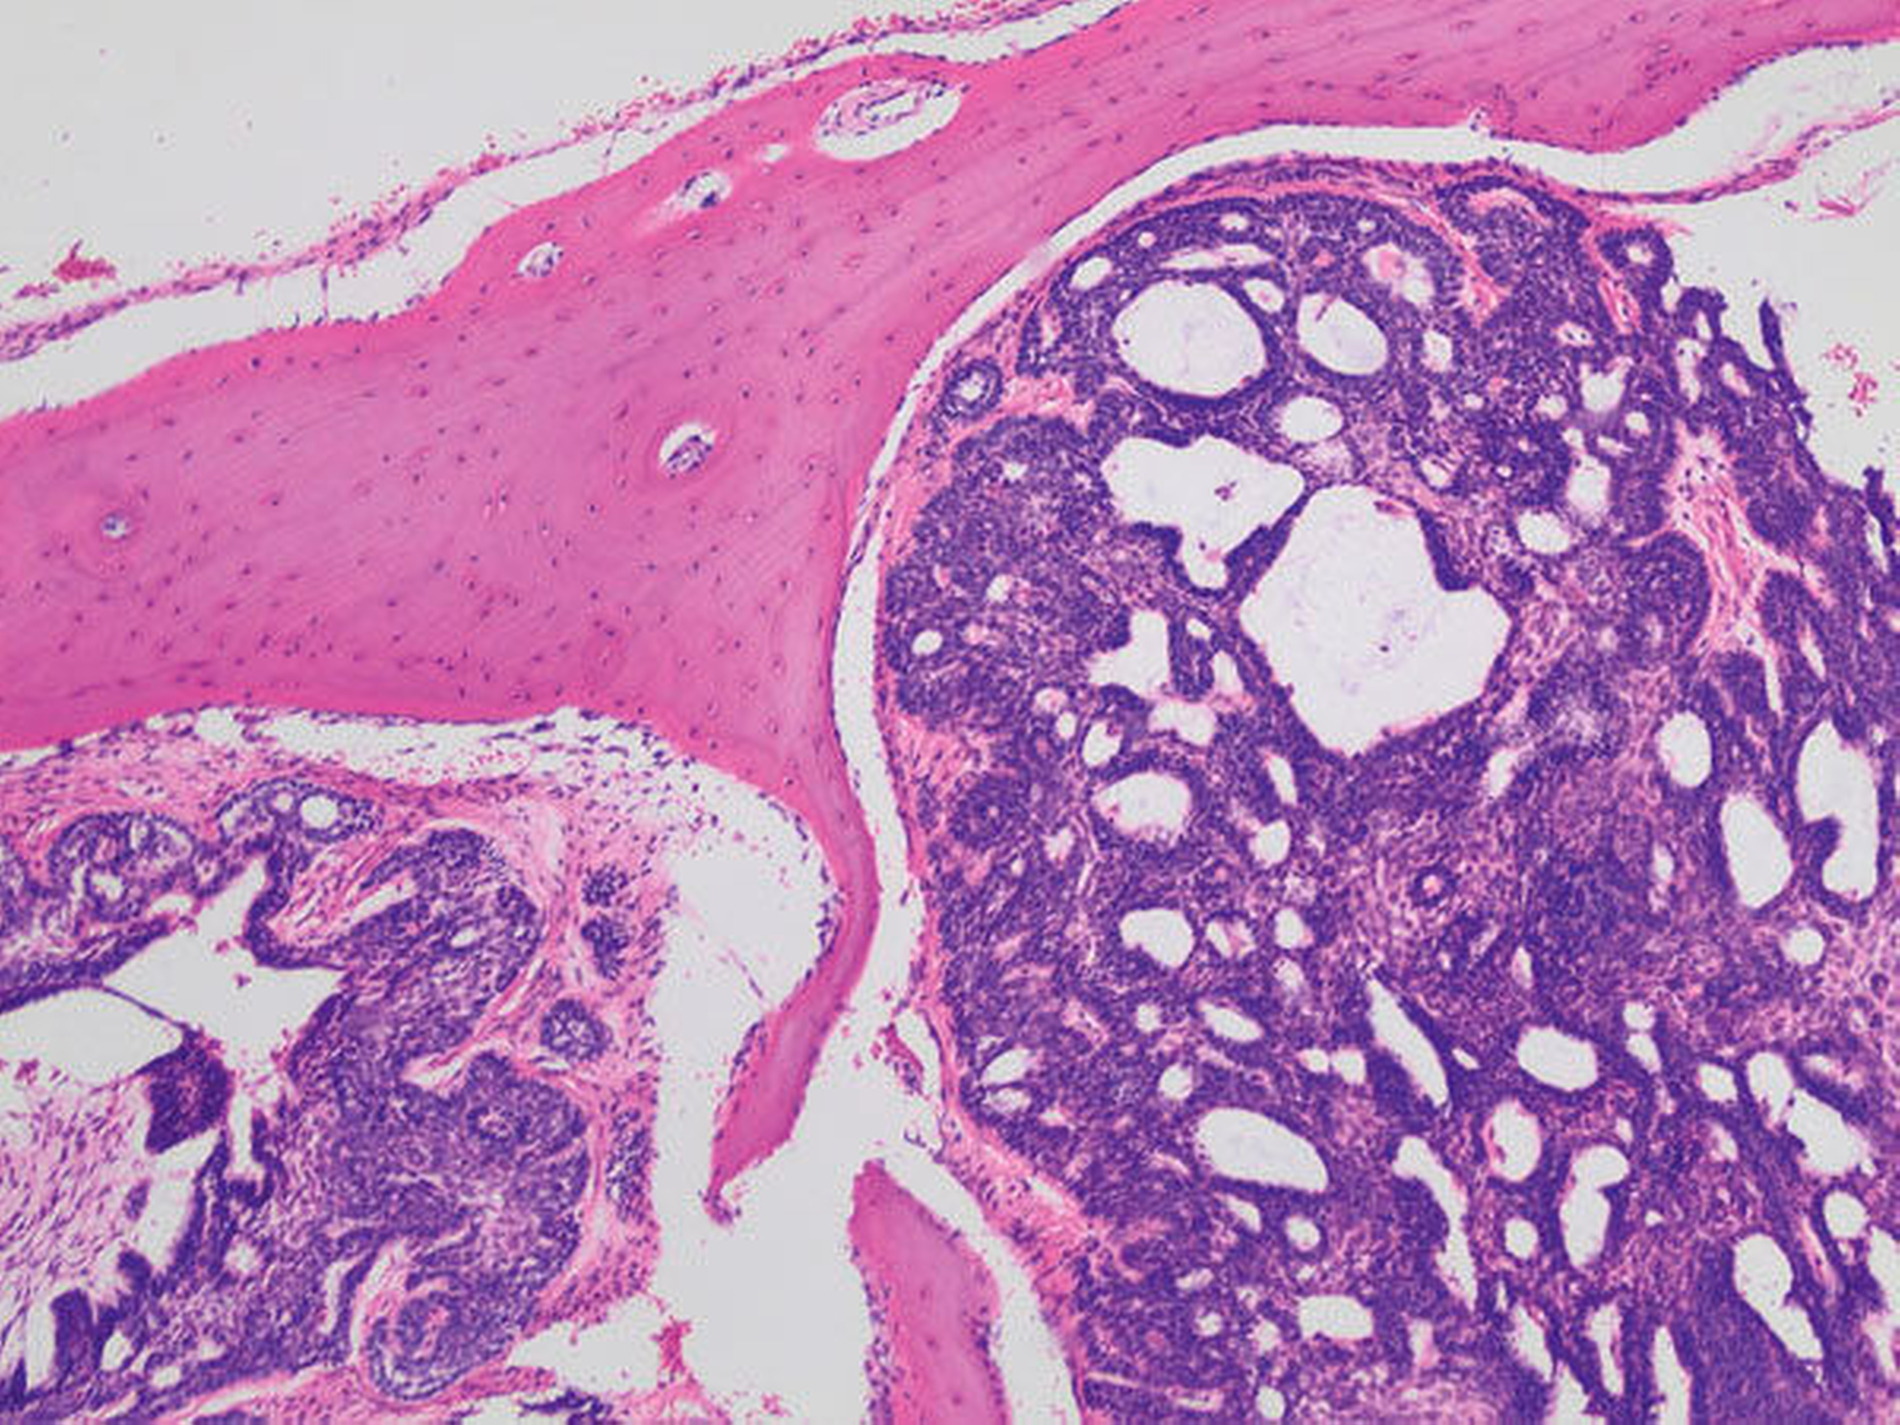

Der Defekt wurde mit einer lokalen Lappenplastik gedeckt (Abbildung 5), eine vorab angefertigte Verbandsplatte zum Wundschutz eingegliedert. Die abschließende histologische Auswertung (Abbildung 6) bestätigte, dass es sich bei dem kompletten Resektat um das bereits ex domo vor-diagnostizierte, teils plexiforme Ameloblastom handelte. Aufgrund der Größe des Tumors erfolgte ein Staging mittels CT-Thorax und Abdomen, das jedoch keinen Nachweis einer Metastasierung erbrachte. Bei mikroskopisch knappen Sicherheitsabständen nach palatinal sowie an der Nasenscheidewand und zur Orbita hin wurde die Patientin über ein differenzial-therapeutisches Vorgehen mit radikal-chirurgischem Vorgehen versus engmaschige klinische und radiologische Nachkontrollen aufgeklärt. Die Patientin entschied sich nach eingehender Aufklärung für die engmaschigen Nachkontrollen. Eine ossäre Rekonstruktion (Abbildung 7) wird derzeit von der Patientin nicht gewünscht.